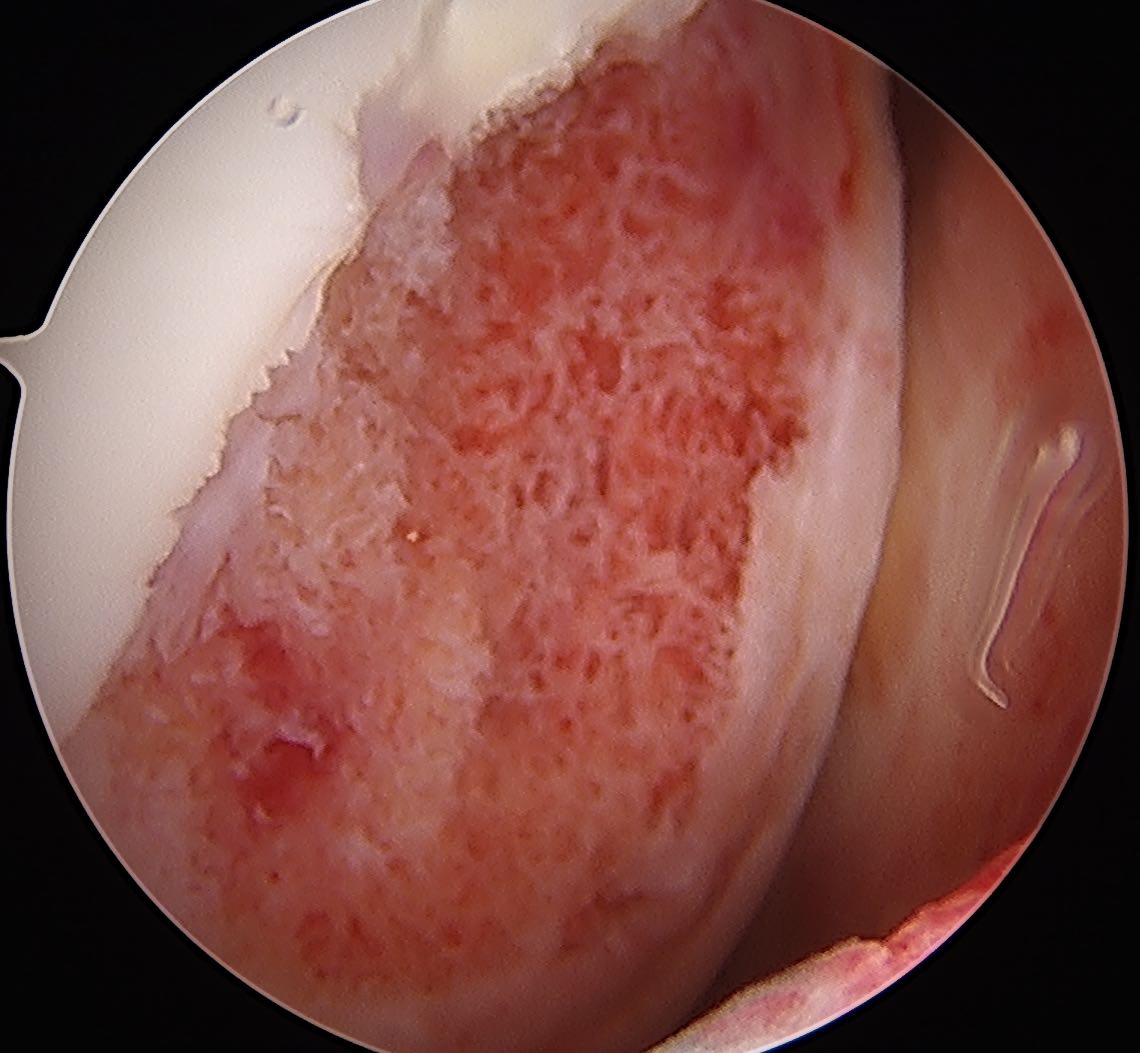

In a stage 1 lesion there is no cartilage breach

- the MFC / LFC looks normal

Transarticular drilling of LFC OCD

Transarticular drilling of MFC OCD